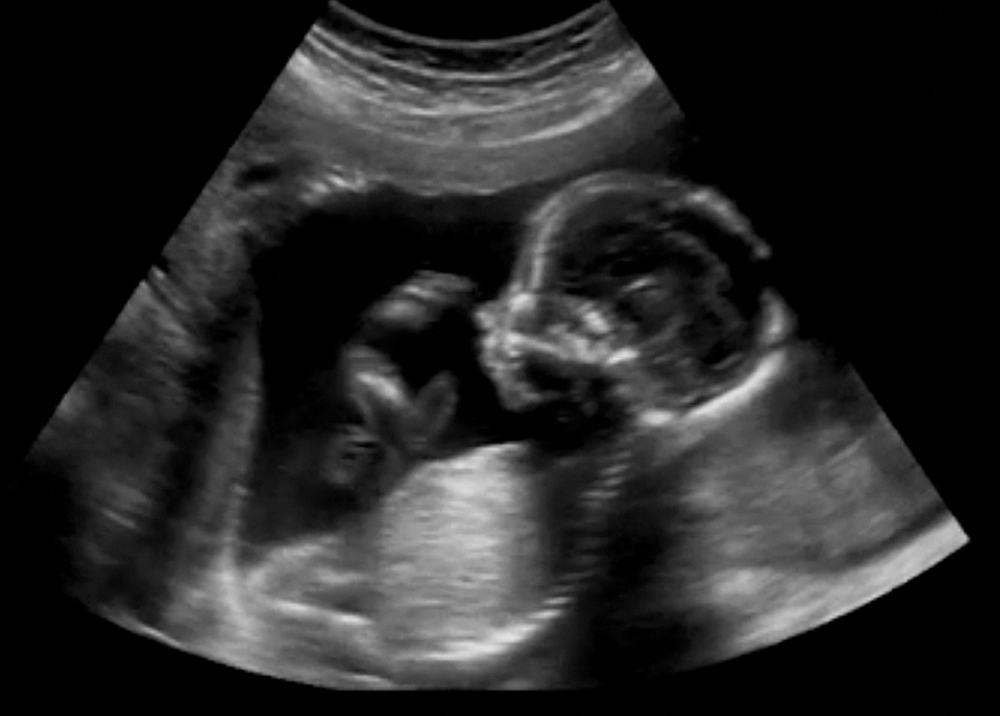

Masa kehamilan merupakan masa yang rentan, sehingga ibu harus bisa memerhatikan kesehatan diri dengan lebih baik untuk mencegah terjadinya komplikasi kehamilan. Sindrom HELLP merupakan salah satu komplikasi kehamilan yang patut diwaspadai selama masa kehamilan. Tanpa pengobatan yang tepat dan cepat, kondisi ini bisa berakibat fatal bagi ibu dan janin. Apa itu sindrom HELLP? Sindrom HELLP atau HELLP […]